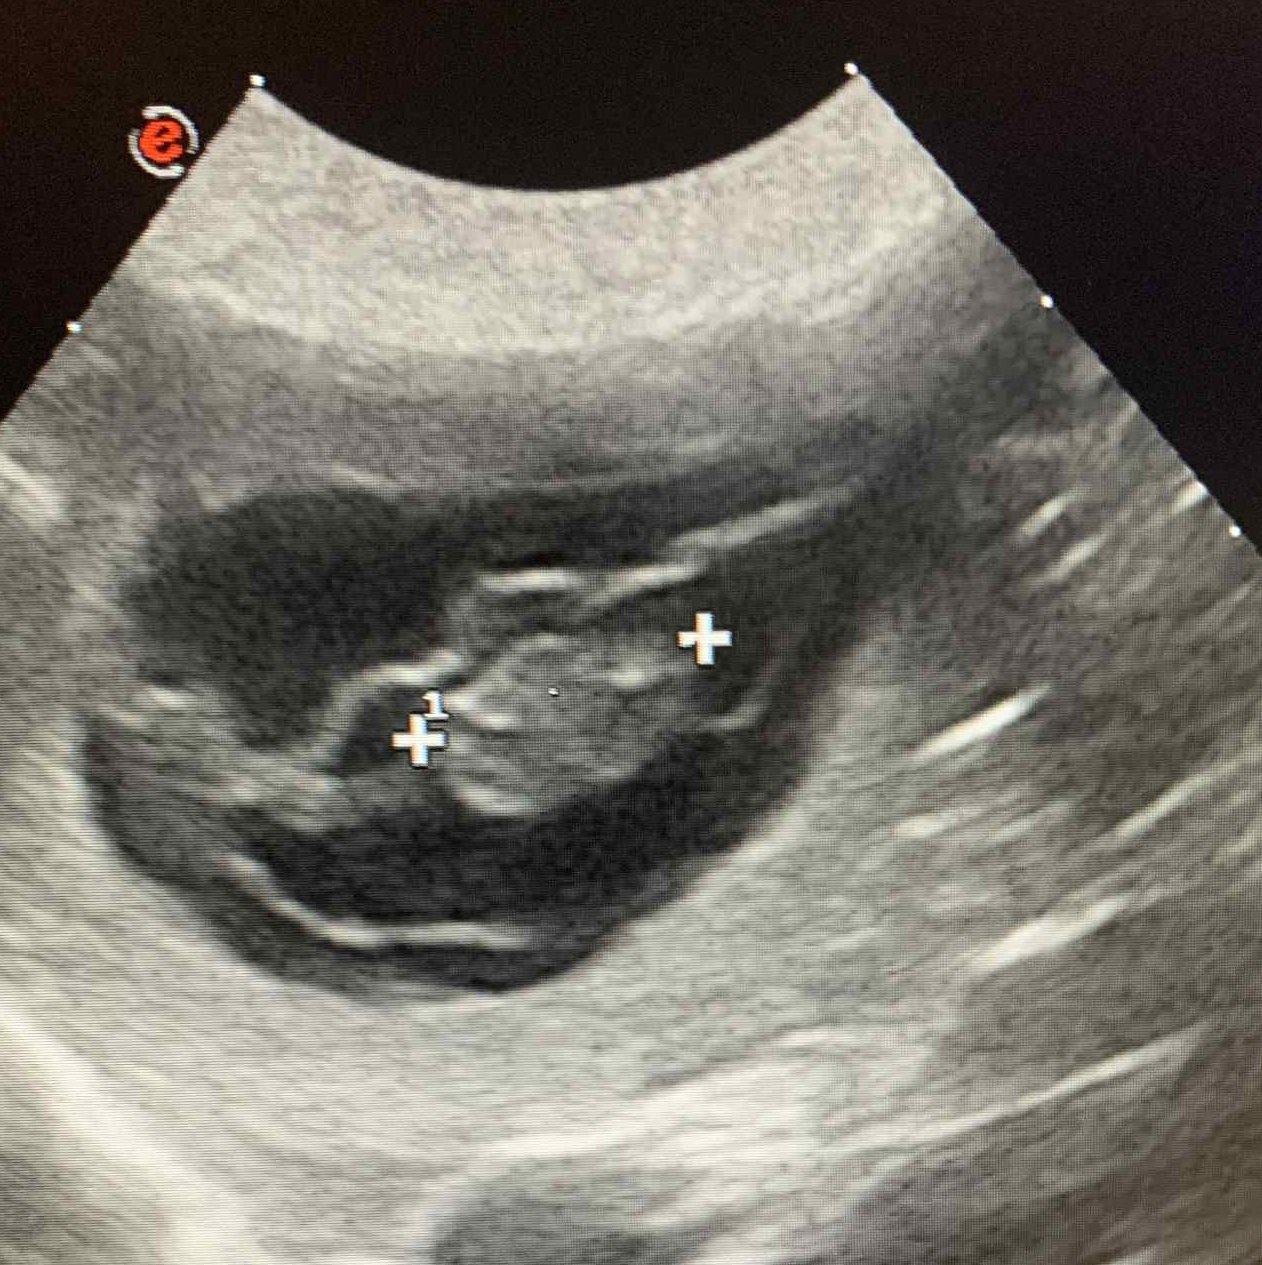

Březost Ziry potvrzena! Ultrazvuk ukázal minimálně 4 štěňátka a my se moc těšíme! Rodiče štěňátk ke zkouknutí zde: Zira a Ero...